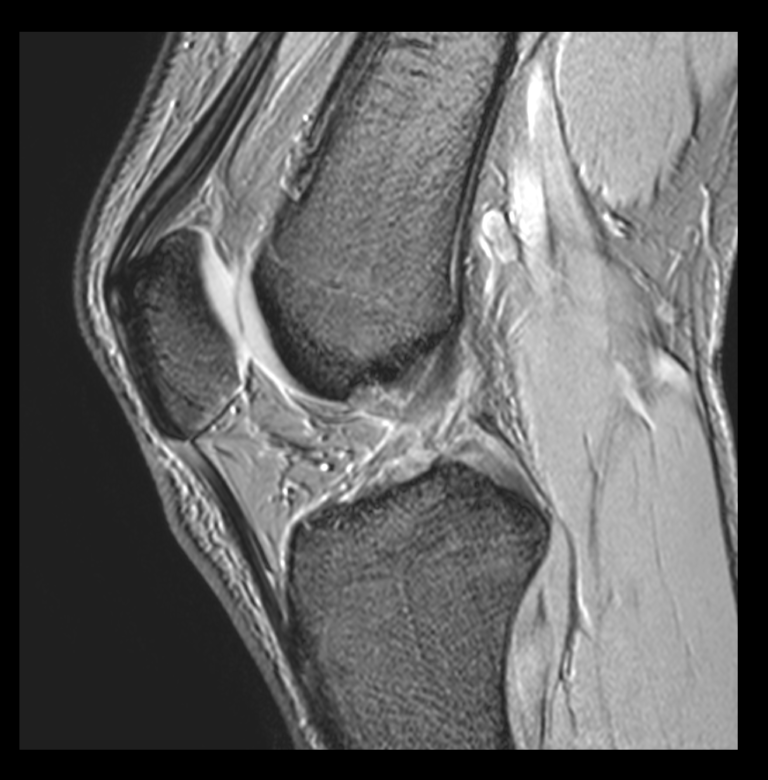

★ 膝関節の衝撃を吸収する組織である膝蓋下脂肪体は重度変形膝では委縮していることを明らかにしました!(2022.05.19) 新潟医療福祉大学 理学療法学科

膝蓋下脂肪体炎とは、膝のお皿(膝蓋骨)の下に膝蓋骨と脛骨をつなぐ腱があり、その深層に脂肪組織の膝蓋下脂肪体があります。. 立ち上がる時や膝の曲げ伸ばしに膝のお皿の下が痛くなる。. また、膝のお皿の下を押すと痛いなどの症状があり.. 実は、膝蓋下脂肪体は炎症が起きると血管がすぐにできてしまい、そしてそこに神経も一緒になって増えます。 私も今までこの「ひざ前方の痛み」の患者さんを治療してきました。 10代や20代の若い方が多いです。 このような方は、軟骨にも異常がなく、半月板にも異常がなく、精神的な面が原因ではとして、お医者さんからも家族からも「本当に痛いの? 」とうがった目で見られてしまいます。 ところがこれは、「不要な血管が痛い」という観点からみると、膝蓋下脂肪体が痛みの原因になっていることは一目瞭然な場合があります。 そうであれば、治療法は、「運動器カテーテル治療」が良いです! 治療については モヤモヤ血管について を参考にしてください。